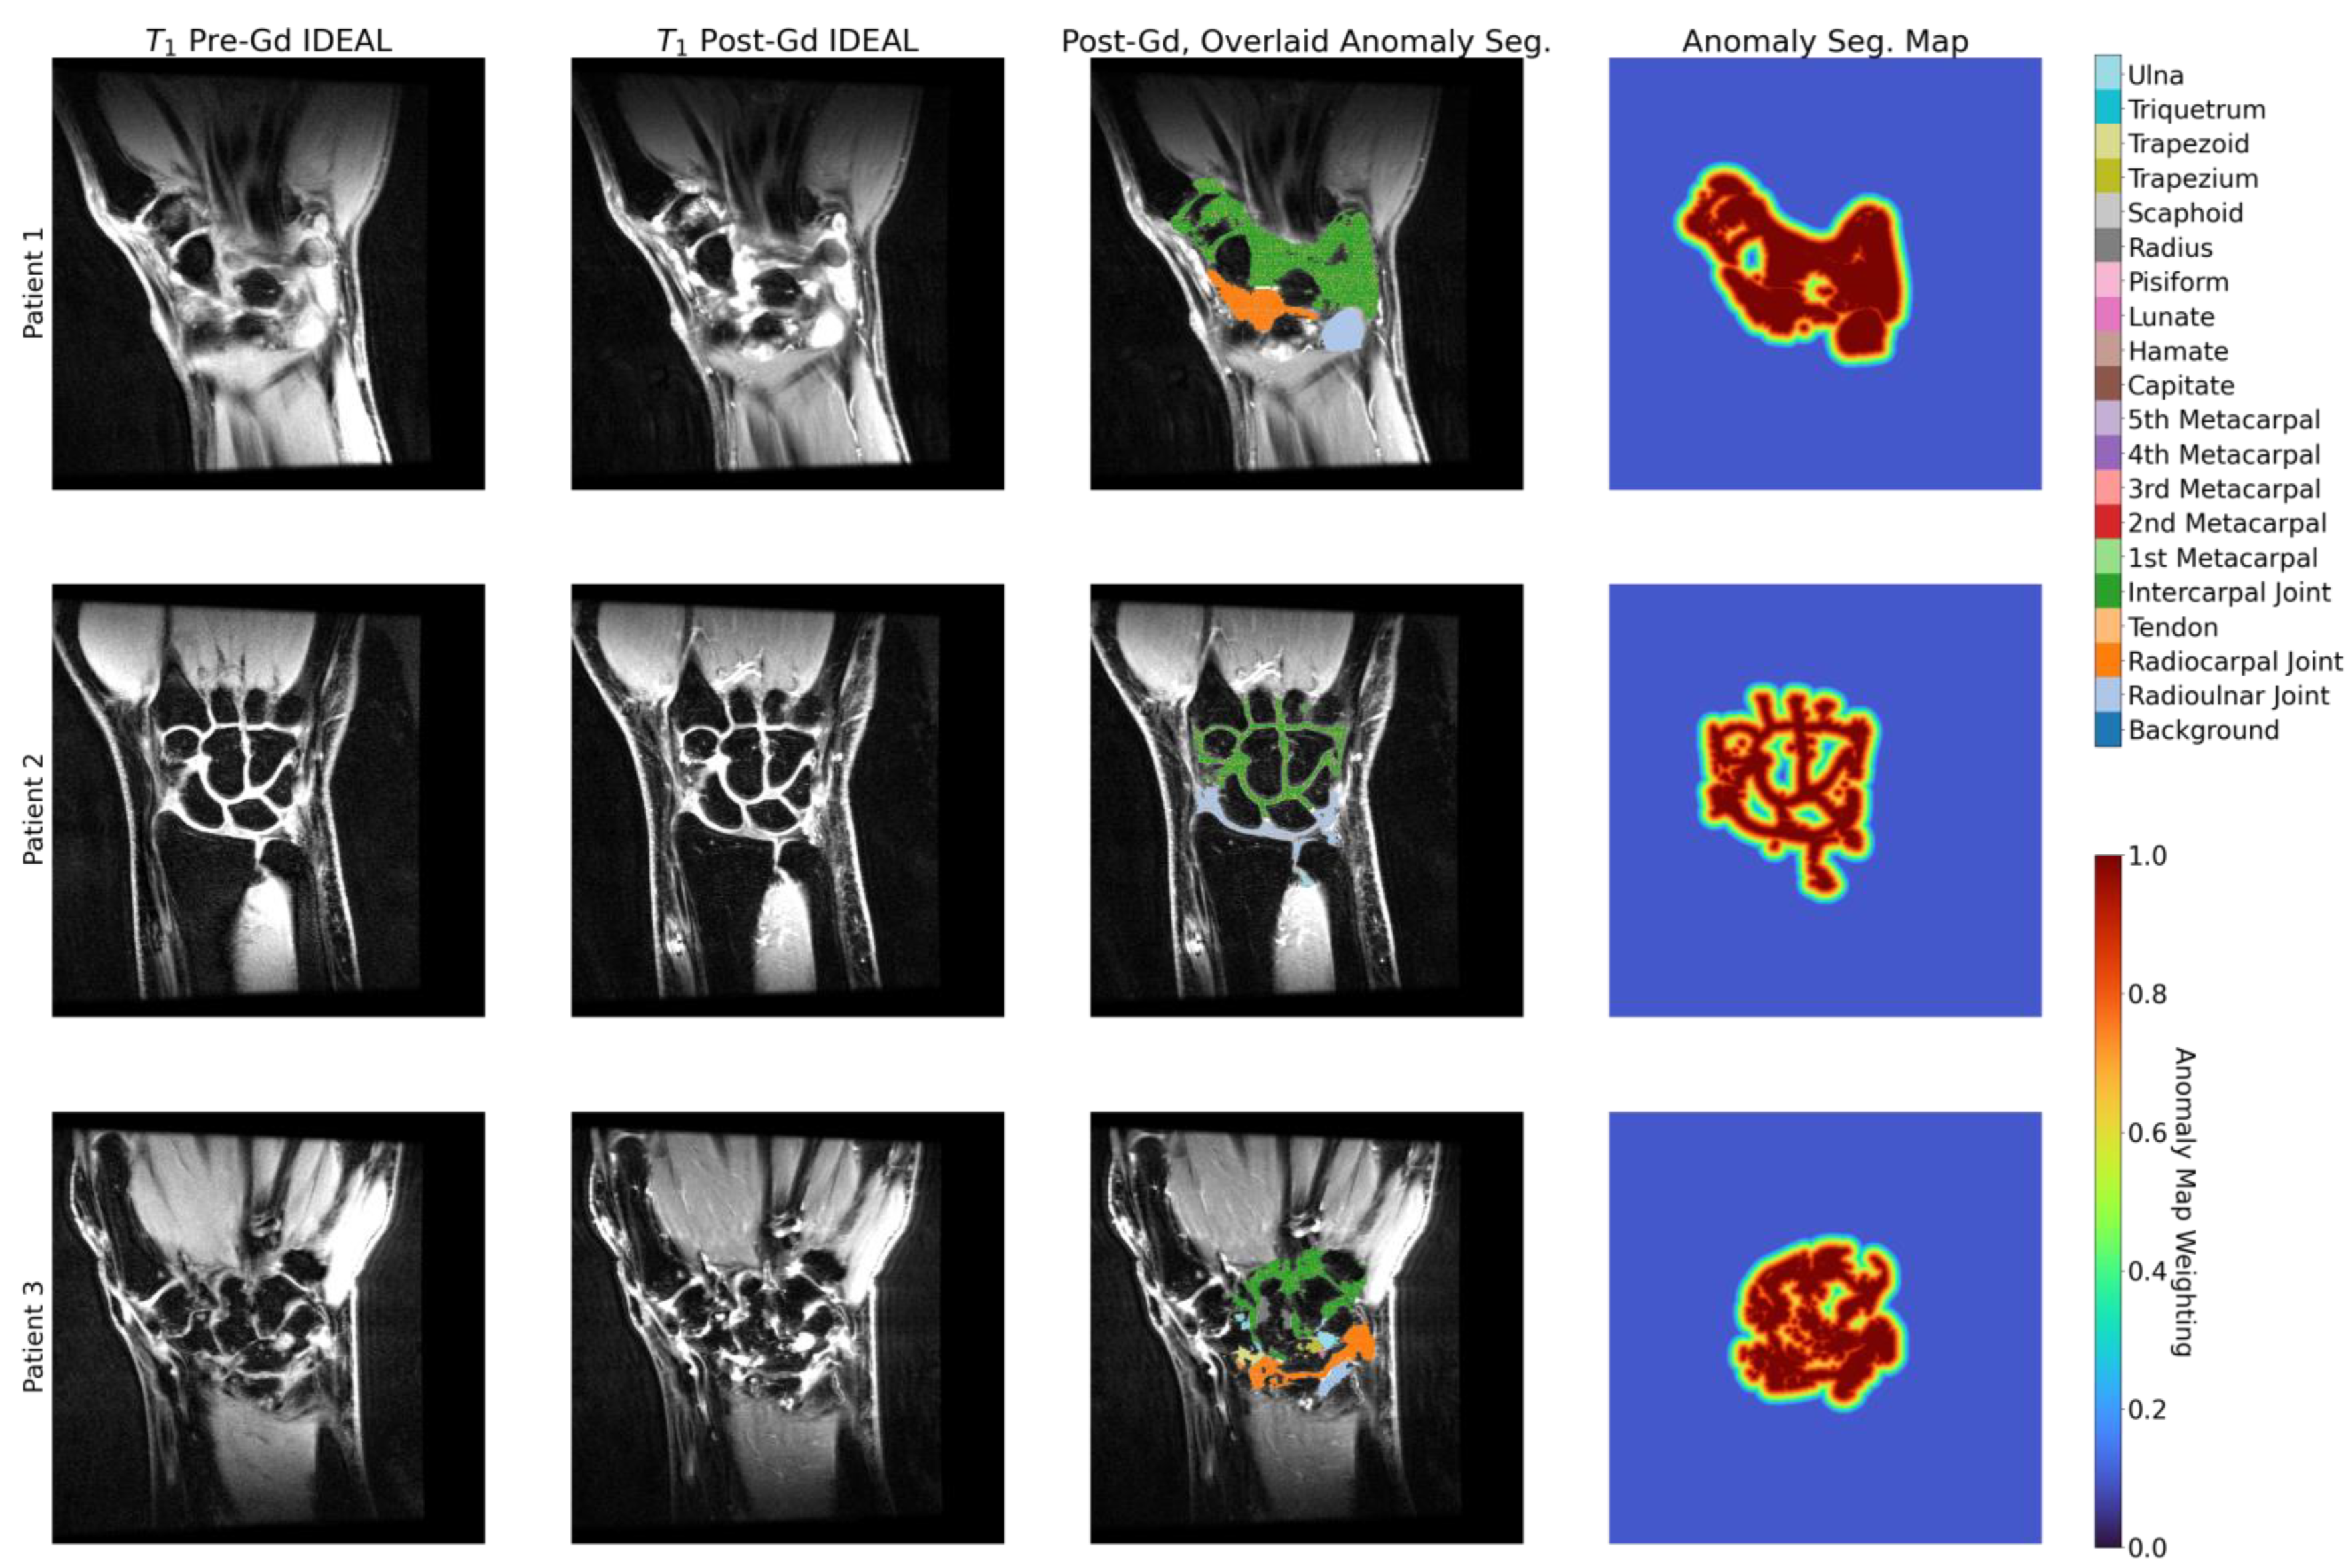

2.3. Anomaly Segmentations and Evaluations

3.5. Enhancement Maps Analysis